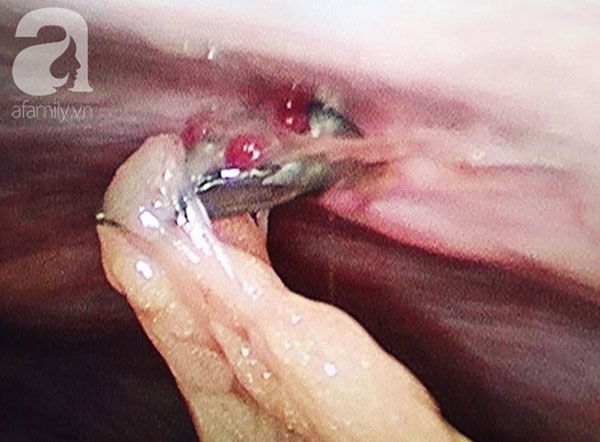

Bệnh nhân được chuyển sang phòng mổ tiến hành mổ nội soi thám sát. Kết quả nội soi cho thấy dù mũi đinh đâm xuyên thành bụng, vào tới ổ bụng nhưng rất may mắn bệnh nhân không bị thủng các tạng tại vị trí đó như: dạ dày, ruột non hay đại tràng góc lách.

Sau khi nhận định được tình hình, các bác sĩ đã nhanh chóng tiến hành rút đinh, ổn định tinh thần và cầm máu cho bệnh nhân.